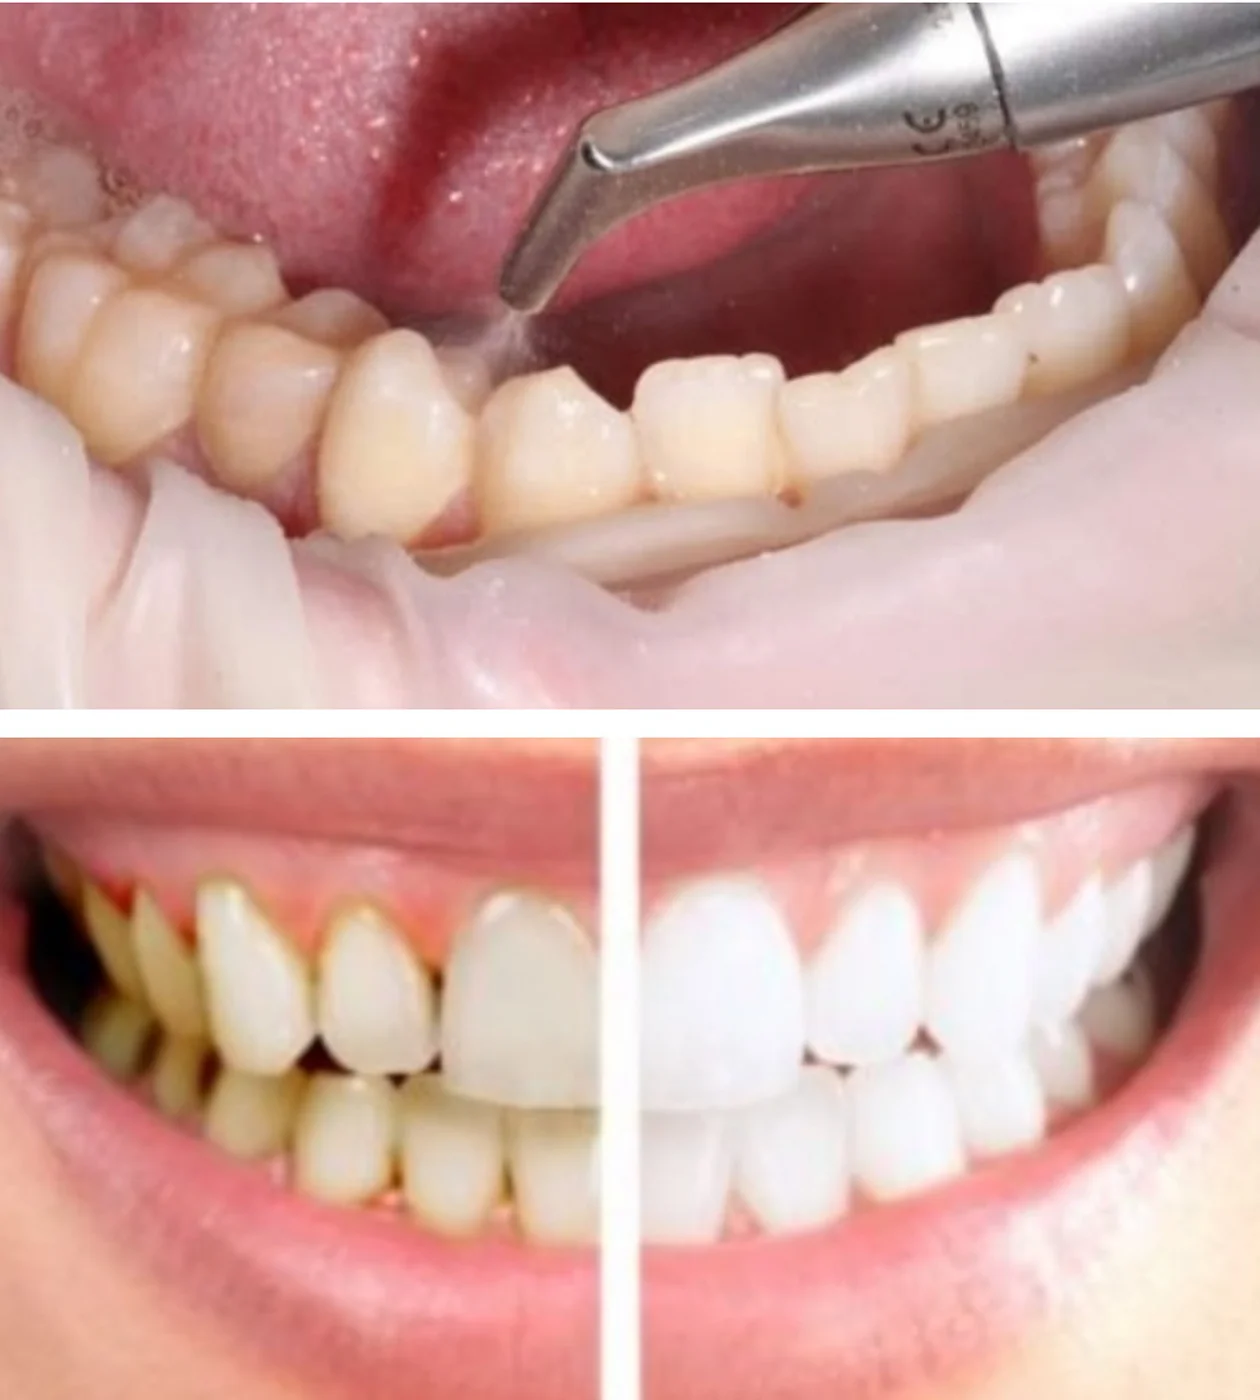

Професійна гігієна по протоколу SRP

Глибоке очищення зубів і ясен від нальоту та каменю для профілактики захворювань пародонту та запобіганню розвитку карієса.

ПАРАДОНТОЛОГІЯ

Лікування захворювань ясен та парадонта (гінгівіт, парадонтит, парадонтоз). Терапія згідно протоколів доказової медицини.